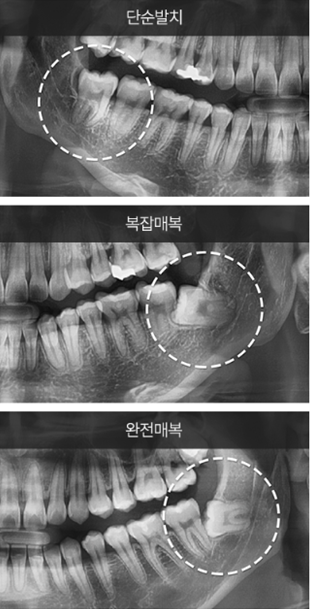

사랑니 종류를 먼저 알아야 합니다.

첫 번째는 발치가 필요 없는

바른 사랑니입니다.

바른 사랑니는 어금니의 기능을 수행하곤 합니다.

두 번째는 잇몸에 일부 묻혀 있는

반매복 사랑니입니다.

반매복 사랑니는 충치와 염증 발생률을 높입니다.

세 번째는 잇몸에 완전히 묻혀 있는

매복 사랑니입니다.

매복 사랑니는 치성낭종을 발생시킬 수 있습니다.

네 번째는 잇몸 속에 비스듬히 묻혀 있는

수평 사랑니입니다.

수평 사랑니는 인접 치아에 통증을 유발합니다.